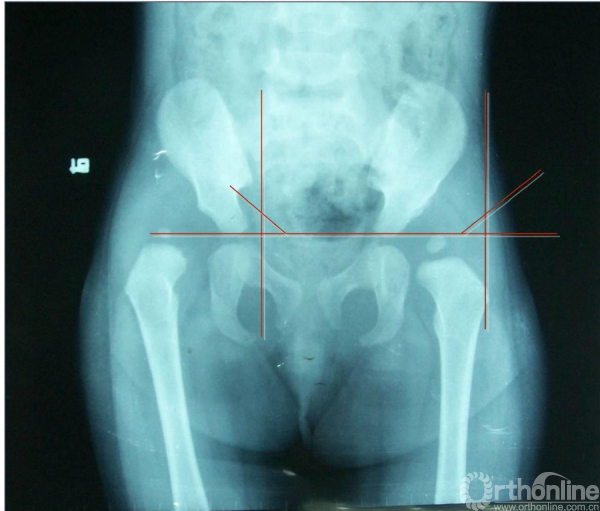

X线检查(髋臼指数)

髋臼指数:又称髋臼角,即髋臼顶的斜度。沿双侧髋臼“Y”型软骨交点作水平连线,再沿髋臼上下缘作切线,两线相交之角即为髋臼角。髋臼角正常值1岁以下为30°,1~3岁为25°,3岁以上为20°。一般认为如超过30°则有明显脱位趋向,可认髋臼发育不良。但在诊断上不能单看髋臼指数一项。

右髋关节Ⅱ度脱位、左髋关节半脱位